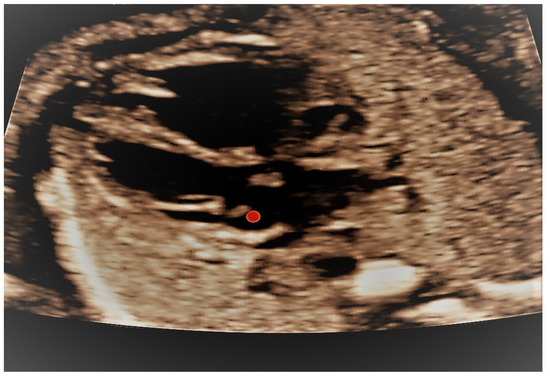

4.1. Case 1